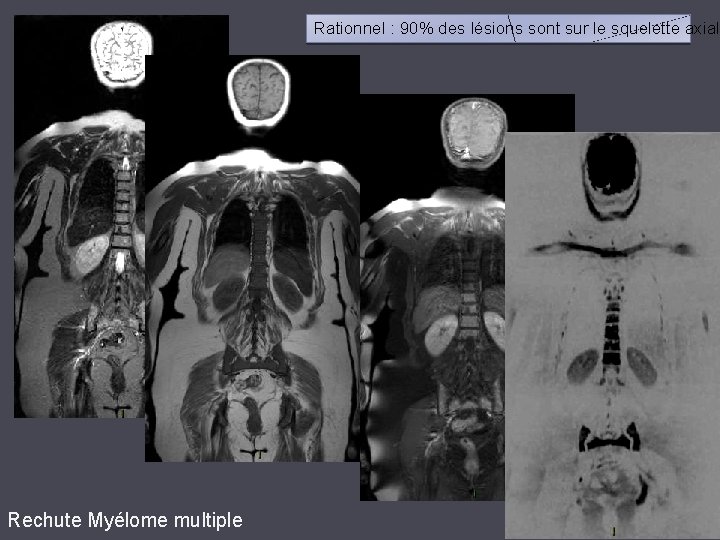

Rationnel : 90% des lésions sont sur le squelette axial Rechute Myélome multiple

Acquisition dans un plan CORONAL Choix non recommandé : acquisition coronale sensible aux artéfacts (épaules, bordure de champ). MIP - acquisition coronale 7

Acquisition dans un plan AXIAL Meilleure solution, artéfacts rares correspondant souvent à des structures anatomiques (ganglion cervicaux, canal rachidien…). MIP - acquisition axiale 8